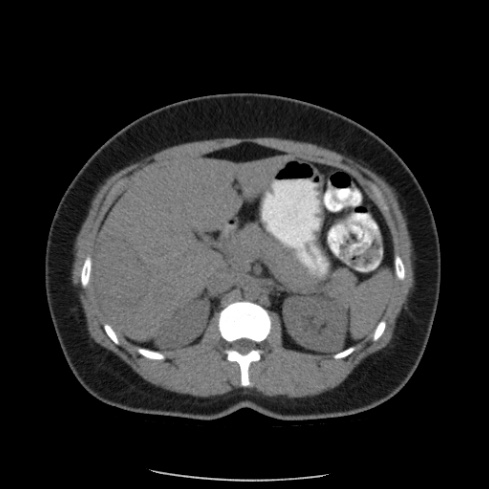

Paciente de 66 años con antecedente de pancreatitis, tomografía control.